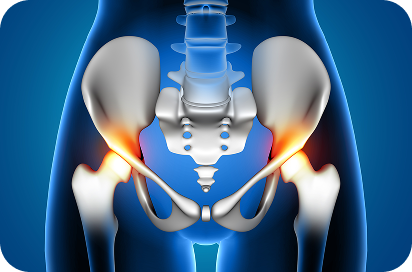

Restore Comfort and Mobility Hip replacement surgery restores function to a damaged hip joint, helping you live without pain and move freely again.

Why Choose Hip Replacement Surgery?

- Personalized Care

- Improved Mobility

- Faster Recovery